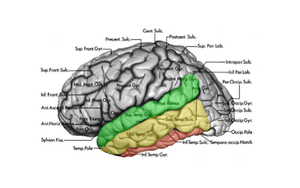

[[Fil:LatTempGyri.png| | [[Fil:LatTempGyri.png|300px|thumb|right|Fig.2 Grøn = gyrus superior (T1), Gul = Gyrus medius (T2), Rød= Gyrus Inferior (T3)]] | ||

Lateralsiden

Lateralsiden af temporallappen udgøres af tre gyri adskilt af to sulci (Fig. 2). Gyrus superior (T1) og gyrus medius (T2) adskilles af sulcus superior, mens gyrus medius og gyrus inferior adskilles af sulcus inferior.